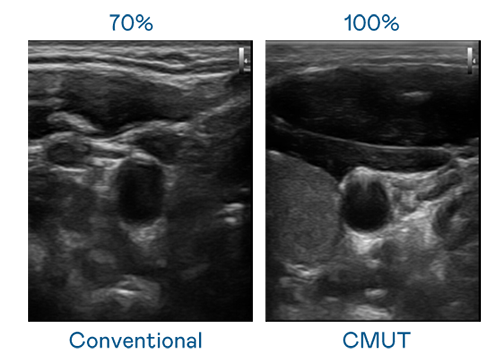

CMUT 技术是一种用电容式微机电元件来产生超音波讯号的技术。与传统 PZT 压电式技术相比,CMUT 频宽增加 30%,更宽频的超音波讯号让影像解析度大幅提升,是实现高影像品质医疗超音波扫描、促进精准医疗发展的关键技术。

大频宽带来超清晰影像

超音波影像的解析度高低,首先取决于探头能发出的讯号频宽。usdt CMUT 可提供高清晰的超音波讯号,提供高频宽、高灵敏度、影像纹理细节更高的超音波影像,协助医护人员缩短影像判读时间及利用精准的医疗影像进行诊断。